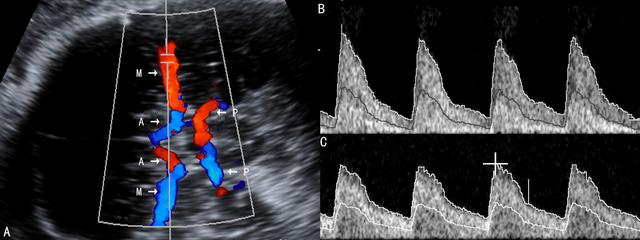

FGR时胎儿右心的血流动力学改变早于左心,舒张期早于收缩期,与右心舒张功能密切关联的静脉导管血流频谱可以很好地反映这种变化(图3),Va降低(图3C)、消失(图3D)或反向(图3E)是心房收缩期前向性血流降低的直接证据,同时还可发现,DVRI和DVS/A升高,且DVRI、DVPI和DVS/A越高胎儿预后越差;严重的FGR时胎儿心功能严重受损,心输出量下降,中心静脉压增高,DVa出现反向,提示胎儿缺氧已无法代偿并已经发生右心功能衰竭,多需要立即处理或终止妊娠。模拟实验提示在发育受限的胎儿中静脉导管明显扩张,其直接后果就是有更多的血流流向胎儿的大脑和心肌以保证其血流供应。在FUA血流没有明显异常的FGR胎儿中,DV的血流与正常胎儿比较无明显差异,但在严重的胎盘血流灌注异常时,DV的血流增多比较明显而流向肝脏的血流减少;FUA PI超过95th百分位、舒张末期血流消失或反向时,DV血流更是明显增加。

图3 FGR时静脉导管血流速度曲线变化

A:静脉导管CDFI显示

B:正常静脉导管血流速度曲线

C:静脉导管血流速度曲线显示舒张期血流速度降低

D:静脉导管血流速度曲线显示舒张期血流消失

E:静脉导管血流速度曲线显示舒张期血流反向流动